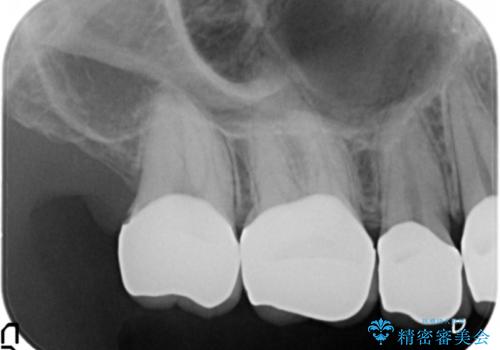

精査したところ、ほとんどの歯が保険内のレジンで充填されており、咬み合わせも悪く咬合していない歯もありました。

虫歯をしっかりと治療したのち、オールセラミッククラウンによる補綴治療を行いました。